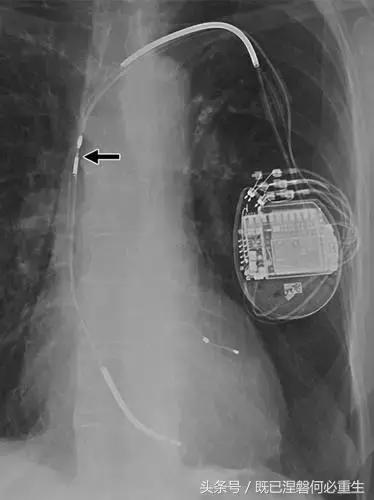

图。 7A 79岁的男性患有电极折断和迁移。

A,初始胸前X线片显示Pacesetter双腔起搏器低于锁骨的心房导线不完全断裂(变薄)(箭头)。

图。 7B 79岁的男性患有电极折断和迁移。

B,大约3年后,电极完全断裂,金属传导碎片(箭头)分离。 远端片段(箭头)已经偏移尾侧,但是由于围绕电极的射线可穿透鞘的约束效应而没有迁移到肺循环中。 引线和中心静脉导管最常见于锁骨和第一肋骨之间断裂,因为它们在臂运动期间被锁骨下肌肉或腱或肋锁韧带压缩[16]。

造成设备故障的最常见的X光检查原因之一是铅断裂。锁骨下静脉经过锁骨下的部位是骨折最常见的位置[16](图7A和7B)。在这个位置的损伤可能发生在导管或导线,并已被描述为锁骨下夹断综合征和锁骨下压溃综合征[16?18]。临床上,骨折的导线通常在患者中产生可以是连续的,间歇的或依赖于患者定位的症状。识别这些状况可能需要挑衅性的动作,例如等长臂锻炼,仰卧或侧向定位或Valsalva。设备检查将显示异常的起搏阻抗(如果绝缘破裂允许导体暴露则减小,如果导体断裂但绝缘完好则增加),感测错误和起搏捕获损失[12]。导线断裂或绝缘损坏可能导致感测或起搏异常。对心律失常的不适当的过感知或欠感应可能导致不适当的治疗,例如抗心动过速起搏和休克治疗,或不适当的抑制治疗。